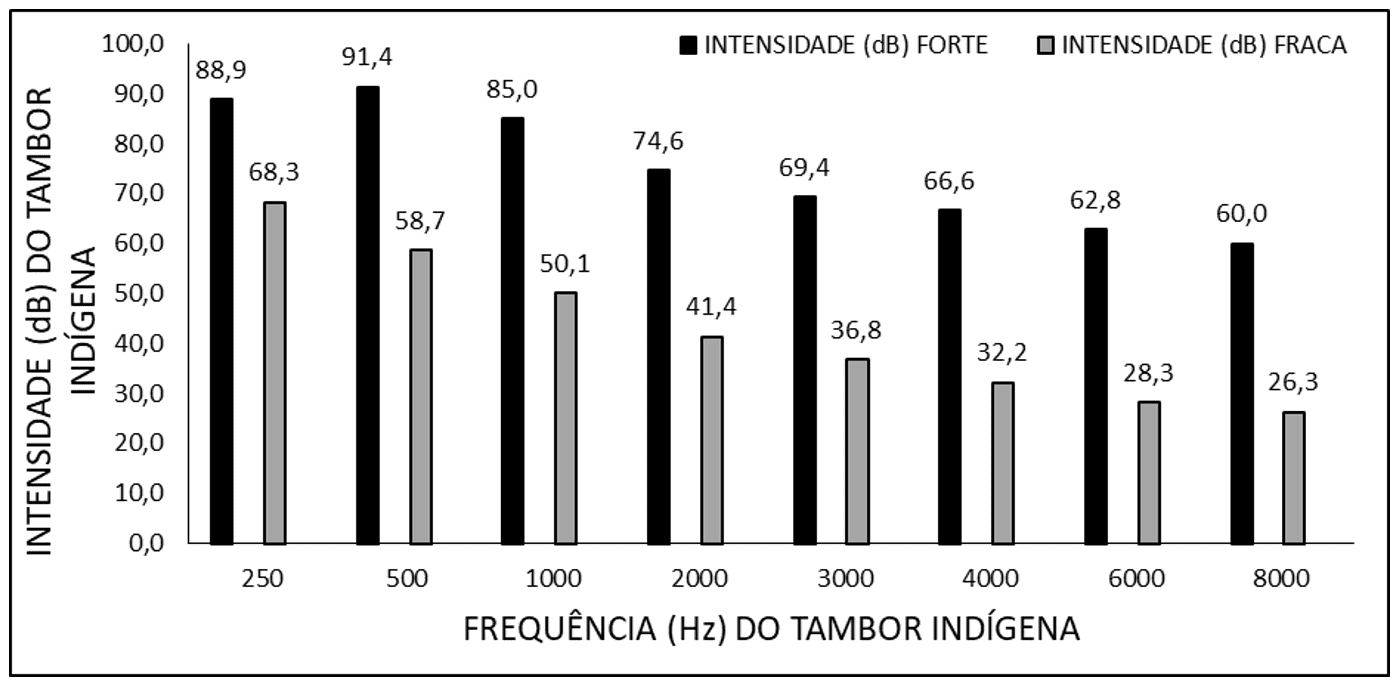

Eficácia de um kit regional indígena amazônico na triagem auditiva neonatal em Belém do Pará

A perda auditiva pode acontecer em diferentes níveis fisiológicos e graus, afetando primariamente as crianças. A Lei nº 12.303/2010